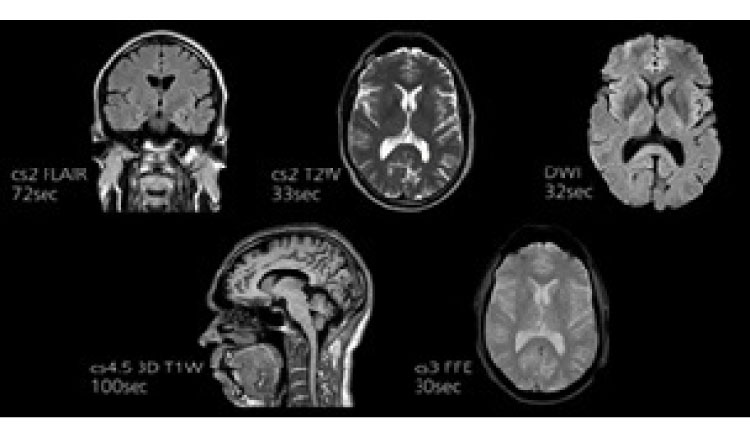

MRI(Magnetic Resonance Imaging:磁気共鳴撮像法)

MRIは、身体を強い磁気の中に置いた状態で、外部から電波を照射すると、体内の水素が反応して信号を発します。その信号を捕らえてコンピュータで解析して画像にします。

CT検査では、身体を輪切りにした画像が主ですが、MRI検査は縦、横、斜めといったあらゆる方向から撮像することができ、またX線被ばくがないので、繰り返し検査することが可能です。

当院には、磁気強度1.5テスラのMRI装置が1台で脳ドック、予約検査、緊急検査を行っています。

ポイント1:『短時間かつ高画質』

AIを用いて高速化、高画質化が可能なソフトウェア“SmartSpeed”を搭載しました。従来装置と同じ時間でより高画質な画像を撮像することや時間を短く設定することが可能になりました。